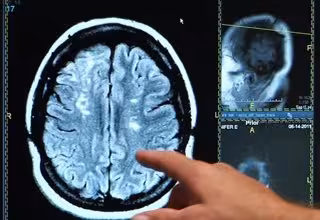

Ictus, derrame cerebral, cerebro

El ictus es la principal causa de muerte y discapacidad, especialmente en los países de bajos y medianos ingresos. Los dos tipos principales de accidente cerebrovascular son isquémico, causado por coágulos de sangre y que representa el 85 por ciento de los infartos cerebrales, y hemorrágico o hemorragia en el cerebro, que supone el 15 por ciento de los accidentes cerebrovasculares.